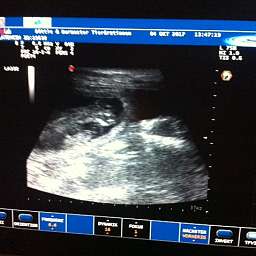

4.10.2017, 35.Tag: Der Ultraschall brachte 5 kleine Wunder zutage. Gesund und munter mit Herzschlag und Bewegung. Elise meisterte alles mit Bravour. Mit Ruhe, Vertrauen und Engelsgeduld ließ sie alles über sich ergehen. Ich bin sehr stolz auf unsere Kleine. Es sind also mindestens 5 Welpen unterwegs. Schaut doch mal:

Eigentlich wollte ich Elise den Ultraschall ersparen. Aber jetzt war es doch wieder ein toller bewegender Moment. Zumindest für mich. Elise liegt jetzt im Körbchen und verarbeitet, was ihr geschehen ist.

Die Ausbildung der Organe ist abgeschlossen. Die Föten sehen jetzt aus wie Hunde; Kopf und Rumpf sind unterscheidbar. Das Geschlecht ist bestimmbar. Der Herzschlag der Föten ist per Stetoskop hörbar....